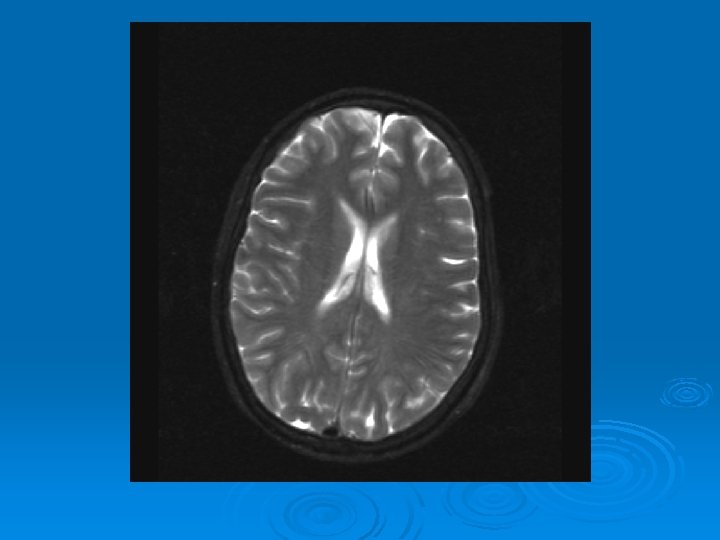

MRI: 2/9/2007 Ø 1. Leptomeningeal enhancement, most prominently seen over the posterior parietal and occipital lobes.

CT head 2/11/07 Ø A right frontal ventriculostomy catheter Ø Diffuse sulcal effacement with thickening of the cortex. Ø Loss of gray-white differentiation and hypodensity in the left parietooccipital region. Ø There is diffuse hypodensity of the cerebellum and brainstem. Ø Ø Ø The basilar cisterns are nearly completely effaced. Ø Impression: Ø Worsened diffuse cerebral edema The lateral ventricles are smaller

CMV: Ventriculoencephalitis Ø Clinical: Can have abrupt presentation of confusion, apathy, impaired memory, withdrawal, nystagmus, motor weakness, cranial nerve deficits, ataxia, seizures, coma. Can rapidly progress. Ø Labs: CSF: Monocytic Pleocytosis, Low Glucose CMV PCR Positive in CSF: (Sensitivity, Specifity 80, 90%, PPV, NPV, 86 -92, 9598%) Serum CMV viremia Ø Ø Ø MRI: Subependymal enhancement, diffuse hyperintense T 2 WI, ventriculomegaly.

MRI of CMV patient Magnetic resonance images of a patient with cytomegalovirus ventriculitis Ependymal enhancement after injection of gadolinium. DPTA seen on coronal T 1 -weighted image. Ø Highly abnormal ependmal signal on proton densityweighted image of the brain in axial section. Ø Ø See images in: l Arribas et al, Cytomegalovirus Encephalitis, Annals of Internal Medicine, 1996, Vol 125, Issue 7